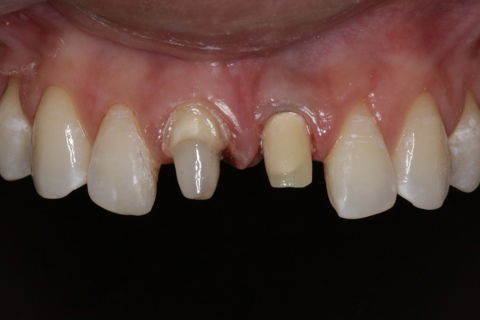

Após 30 dias foi feito o tratamento endodôntico do elemento 11 e cimentação de pino de fibra de vidro e recolocacão do provisório. Depois do tempo previsto de osteointegração do implante, partimos para segunda fase do tratamento que seria o preparo do elemento 11 para coroa total e moldagen dos elementos para confecção de coroa sobre dente e coroa sobre implante em emax (dissilicato de lítio ) como mostra nas FIGURAS 6 e 7.